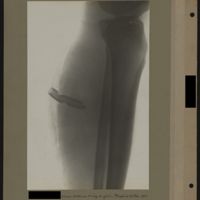

0038 - Page 34 - [Radiographie du fémur]0038 - Page 34 - [Radiographie du fémur]

0053 - Page 49 - [Radiographie du fémur]0053 - Page 49 - [Radiographie du fémur]

0055 - Page 51 - [Radiographie du fémur]0055 - Page 51 - [Radiographie du fémur]

0056 - Page 52 - [Radiographie du fémur?]0056 - Page 52 - [Radiographie du fémur?]

0057 - Page 53 - [Radiographie du fémur]0057 - Page 53 - [Radiographie du fémur]

0090 - Page 86 - [Radiographie du fémur]0090 - Page 86 - [Radiographie du fémur]

0093 - Page 89 - [Radiographies du fémur]0093 - Page 89 - [Radiographies du fémur]

0099 - Page 95 - [Radiographies du fémur]0099 - Page 95 - [Radiographies du fémur]